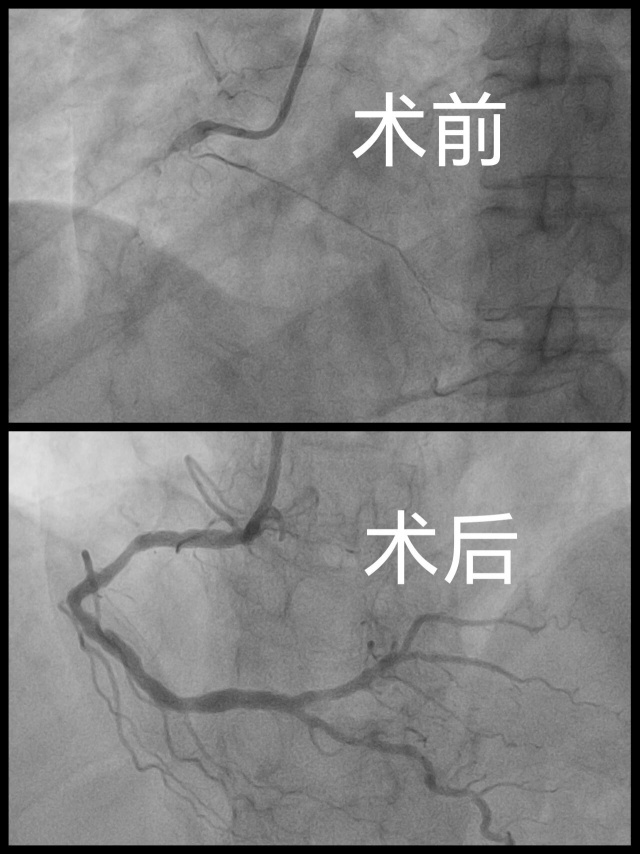

另讯:全天学术会议接近尾声之际,山东中医药大学附属医院胸痛工作群又传来了急救信息,两例急性ST段抬高型心梗患者同时由120送达分别送至东、西两院区。时间就是心肌,时间就是生命!胸痛中心一键启动急性心肌梗死救治流程,与会团队即刻分兵两路,从会场赶往医院,两区导管室同步备台、同时手术,仅用时30余分钟即成功开通闭塞血管,为患者赢得宝贵生机,与会专家见证了山东中医药大学附属医院实时救治急性心肌梗死患者的专业水平,充分展现“山东中西医结合胸痛联盟”理事长单位高效协同的救治能力。

▲急诊手术患者术前术后造影结果